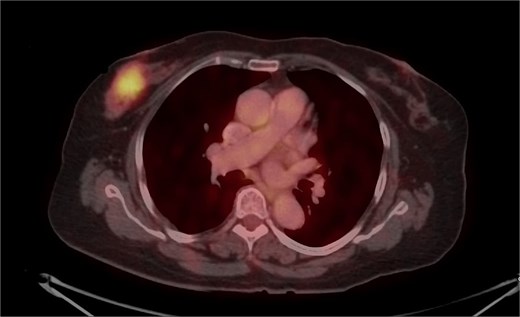

Mammography revealed an asymmetrical density in the upper outer quadrant of the right breast with BIRADS V classification. Ultrasonography identified an irregular hypoechoic lesion measuring 3.8 × 2.5 cm in the right breast. Additionally, multiple enlarged axillary lymph nodes with cortical thickening were seen, the largest measuring 1.02 cm in diameter. A core needle biopsy of the breast lesion demonstrated features of invasive carcinoma, not otherwise specified (NOS), Grade II based on the Nottingham grading system. Immunohistochemistry revealed the tumor to be ER-positive (78%), PR-negative, Her2Neu-negative, and Ki67–21%, confirming it as Luminal A subtype. The excised axillary lymph nodes exhibited caseating granulomatous inflammation, consistent with tuberculosis (Fig. 1). Acid-fast bacilli (AFB) testing further confirmed the diagnosis of TB. Pre-surgical imaging revealed metabolically active areas in the breast lesion and axillary lymph nodes with no evidence of systemic metastases (Figs 2 and 3).

PET-CT axial view of the thorax, indicating a metabolically active lesion in the right breast.

PET-CT axial view of the thorax, indicating a metabolically active lesion in the right axillary region, involving the right axillary lymph nodes.